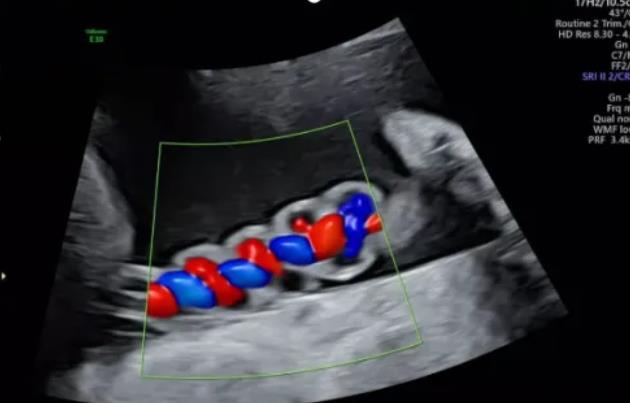

漯河市中醫(yī)院健康科普:超聲檢查之臍帶螺旋

聲像圖特征:臍動(dòng)脈表現(xiàn)為過(guò)度螺旋,臍血管變細(xì),縱切面呈“麻花狀”,橫切面呈“鼠眼狀”;

2、臍帶螺旋過(guò)松

聲像圖特征:胎兒臍帶縱切面示血管呈平行排列,螺旋稀少,彩色多普勒血流成像示臍帶血管內(nèi)充滿的紅藍(lán)血流呈平行排列,麻花狀螺旋消失。